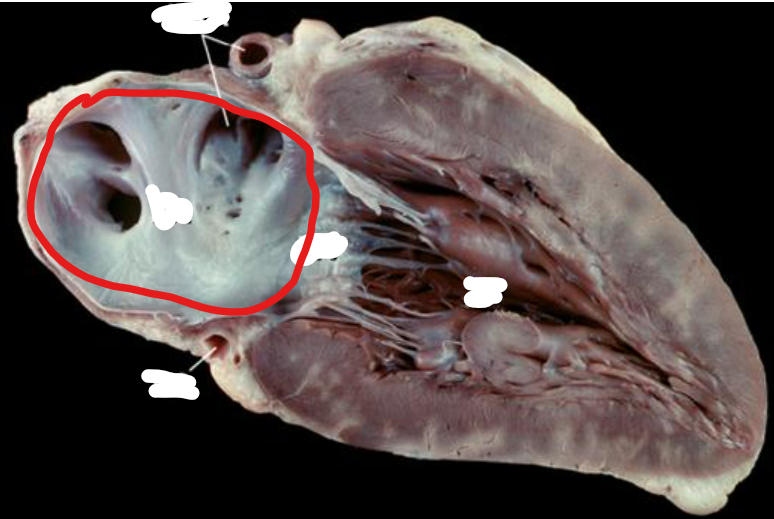

Q

Name the valve and list the components of the valve

Aortic Semilunar Valve

nodule

lunulae

cusps

1

Name this structure. What is the term for the structure it is on?

A

Fossa Ovalis

Interatrial Septum

16

Opening of Inferior Vena Cava

How well did you know this?

17

Opening of Superior Vena Cava